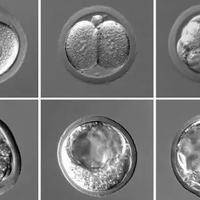

说到做试管婴儿,不少朋友都会问:“哪家医院的成功率最高啊?” 这问题听起来简单,但实际上挺复杂的。试管婴儿技术现在越来越普及,给很多家庭带来了新希望,但成功率这事儿,真不是一句话能说清楚的。咱们今天就来聊聊这个话题,帮你理清思路,找到最适合自己的选择。试管婴儿成功率没有哪家医院能保证百分之百的成功率。成功率这东西,影响因素多着呢。比如,患者的年龄就是个大关键。年纪轻一些,卵子质量好,成功率自然就高

“明明是评分不错的优胚,怎么养囊就失败了?”这是很多试管家庭面临的困惑与遗憾。不少人把优胚等同于“养囊保险箱”,失败后便陷入自我怀疑,甚至盲目要求重复养囊。其实,优胚养囊成功率虽高于普通胚胎,但从不是100%——养囊是胚胎“优胜劣汰”的过程,不成功可能是胚胎内在潜力不足,也可能是培养环境的细微影响。此时最该做的不是焦虑,而是结合医学评估,找到科学的应对方向。优胚养囊成功不是必然要理性应对失败,首先